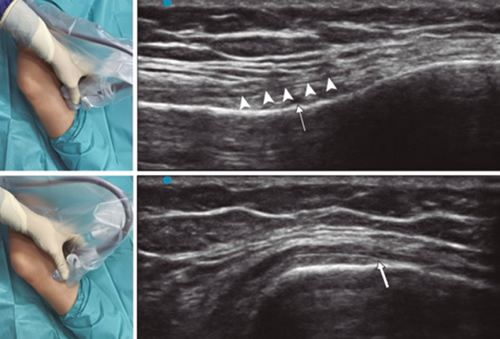

Figura 1

Figura 2

Figura 3

Figura 4